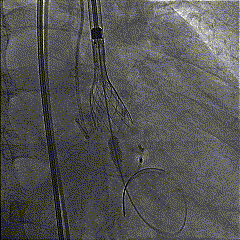

TaurusElite输送系统柔顺过弓跨瓣后,AV26瓣膜瓣环平面定位释放,到工作位后造影瓣膜形态、位置良好,冠脉血流灌注正常;完全释放后瓣膜形态、位置良好,微少量瓣周漏。

定位释放

释放到工作位评估

术后造影

术后压差从38mmHg降到8mmHg,前向血流从3.8m/s降至1.36m/s。